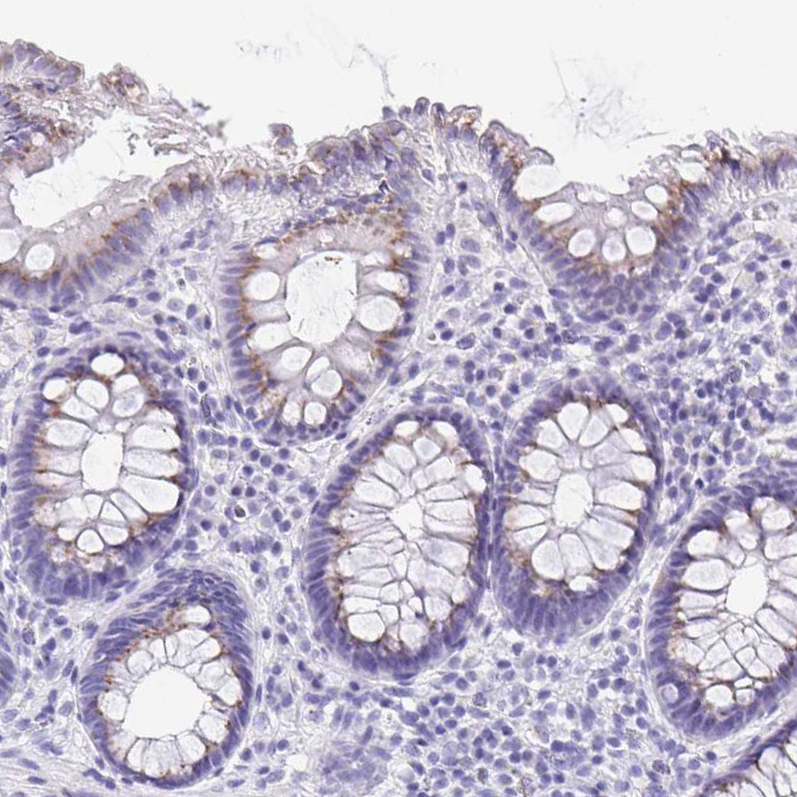

Immunohistochemistry analysis in human small intestine and pancreas tissues using HPA002107 antibody. Corresponding SULT1B1 RNA-seq data are presented for the same tissues.